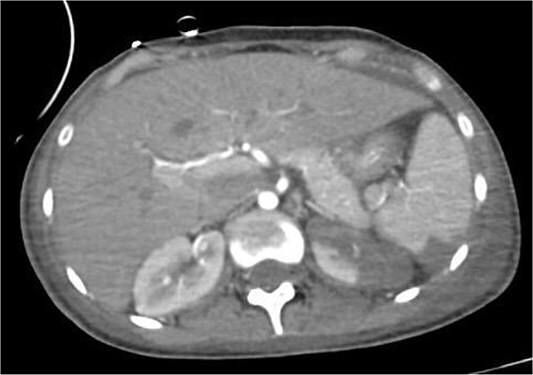

霉菌性动脉瘤(MAs)是感染性心内膜炎(IE)的一种罕见但危及生命的并发症,由感染性心内膜炎栓塞在脑血管内引起并导致动脉瘤形成。本病例报告描述了一名17岁女性在IE治疗期间出现多发性MAs,导致灾难性的神经功能衰退和最终死亡。在接受开胸手术切除植物后,患者因真菌性动脉瘤破裂出现颅内出血,在一次不成功的开颅减压手术后死亡。该病例强调了在IE背景下早期识别和及时干预MAs管理的重要性,以及需要制定方案来改善这些高危患者的预后。MAs破裂相关的高死亡率突出了这些并发症的严重性及其管理的挑战。

Mycotic aneurysms (MAs) are a rare but life-threatening complication of infective endocarditis (IE), resulting from septic emboli lodging in cerebral vessels and leading to aneurysm formation. This case report describes a 17-year-old female who developed multiple MAs during treatment for IE, resulting in catastrophic neurological decline and eventual death. After undergoing open-heart surgery for vegetation excision, our patient then developed intracranial bleeding due to mycotic aneurysms rupture, which led to her death after an unsuccessful decompressive craniotomy. This case highlights the importance of early recognition and timely intervention in the management of MAs in the context of IE, as well as the need for protocols to improve outcomes in these high-risk patients. The high mortality rate associated with ruptured MAs highlights the critical nature of these complications and the challenges in their management.